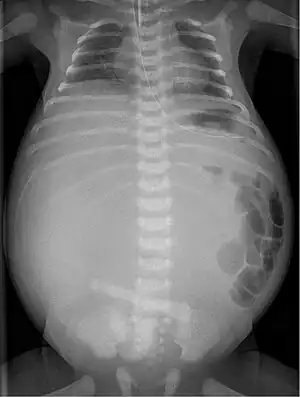

| X-ray of a newborn with meconium pseudocyst resulting from bowel perforation. In this case the cause was atresia of the terminal ileum. There is a fine rim of calcification surrounding the big pseudocyst which shifts the other intestinal structures outwards. | |

In terms of the clinical presentation often it is abdominal distension (at birth)[1]

Twenty percent of infants born with meconium peritonitis will have vomiting and dilated bowels on x-rays which necessitates surgery.